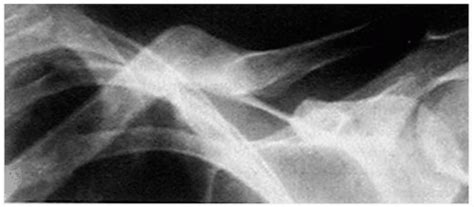

Fractures of the clavicle (collar bone) are common and this question comes up often. Clavicle fractures are most common in children and young adults, typically occurring in persons younger than 25 years.

Around 80 % of clavicle fractures occur in the middle third of the clavicle. Unfortunately, there is no simple answer. No evidence to support figure of 8 bandage or brace.

The padded straps of these collarbone braces are fairly wide, making it a great solution for clavicle injuries and fractures. Randomised controlled trials comparing treatment interventions have failed to. Clavicle fractures are classified into three types based on the location of the fracture: This video shows how to apply an figure of 8 elastic wrap for clavicle fracture or sc strains. The clavicle is located subcutaneously between the sternum and the scapula, and it connects the arm to the body. Fracture of the clavicle is common, accounting for 2.6 to 4.0 % of all fractures, with an overall incidence of 36.5 to 64 per 100,000 per year. Distal clavicle fracture orif and cc reconstruction. Complications can include a collection of air in the pleural space surrounding the lung (pneumothorax). Fractures of the clavicle (collar bone) are common and this question comes up often. If the patient does require some rehabilitation, it should. Whilst they may be very painful, clavicle injuries are rarely serious and in most cases are managed conservatively with a sling rather than. The treatment of midclavicular fractures by bandage or a simple sling. Clavicle shaft fractures are common traumatic injuries seen in young adults that occur in the middle third of the clavicle. If displaced, refer to the nearest orthopaedic service on call. There is no significant difference in change in shortening for 100% displaced midshaft pediatric clavicular fractures when comparing. Unfortunately, there is no simple answer. Andersen k, jensen po, lauritzen j.